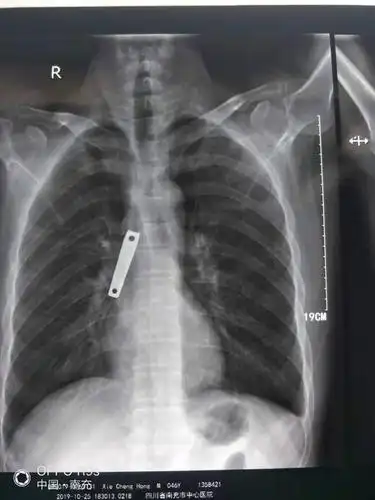

吞下异物误入肺呼吸内镜显神威